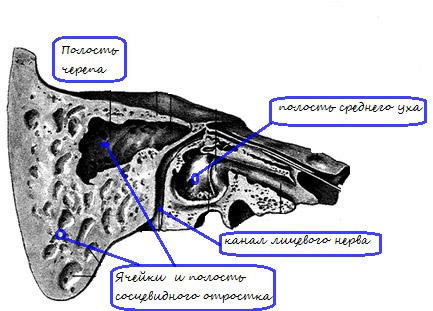

Анатомия сосцевидного отростка